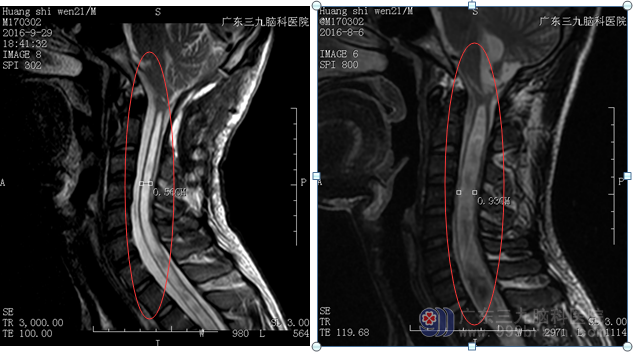

患者黄某,男,21岁,无明显诱因出现右上肢乏力,麻木感,缓慢加重,症状持续1个月,遂到当地医院就诊,行颈部MR提示颈髓空洞症,未予特别处置。今为进一步诊疗,来我院就诊。

患者由神经外二科接诊,完善相关检查,判断,脊髓空洞症形成已排除炎症可能,考虑发育因素可能性大,考虑行空洞切开内引流术。行全麻下脊髓空洞内造瘘术,手术由神经外二科主任林涛主刀完成,电凝切开硬脊膜,脊髓中央管开口明显扩大,表面蛛网膜粘连,枕大池与颅颈交界区粘连明显。给予镜下松解粘连组织,开放空洞与蛛网膜相通,硬脊膜、脊髓膜保护良好。术后留置引流管一枚,缝合。患者经康复训练后,无疼痛、发热、呕吐及肢体抽搐等不适,精神反应良好。出院前查体,精神语明,按吩咐动作,切口愈合甲级,心肺腹均未见明显异常。回访患者,目前情况良好。